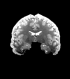

Figure 6: Example field maps (Subject ID 826353) at initialization (top row) and after optimization with Gauss-Newton (bottom row). The first column uses the proposed optimal transport initialization scheme. The middle column uses the same scheme with an additional Gaussian blur to promote smoothness. The right column uses the coarse-to-fine multilevel initialization scheme from HySCO with five levels, and the final field map is optimized at the original image resolution. The multilevel initialized field map is smooth by construction and further optimized to improve the relative image distance at the full resolution. The optimal transport initialization accurately corrects the distortions but is not smooth in the non-distortion dimensions unless blurred with a Gaussian. After the fine-level optimization all field maps are visually similar.